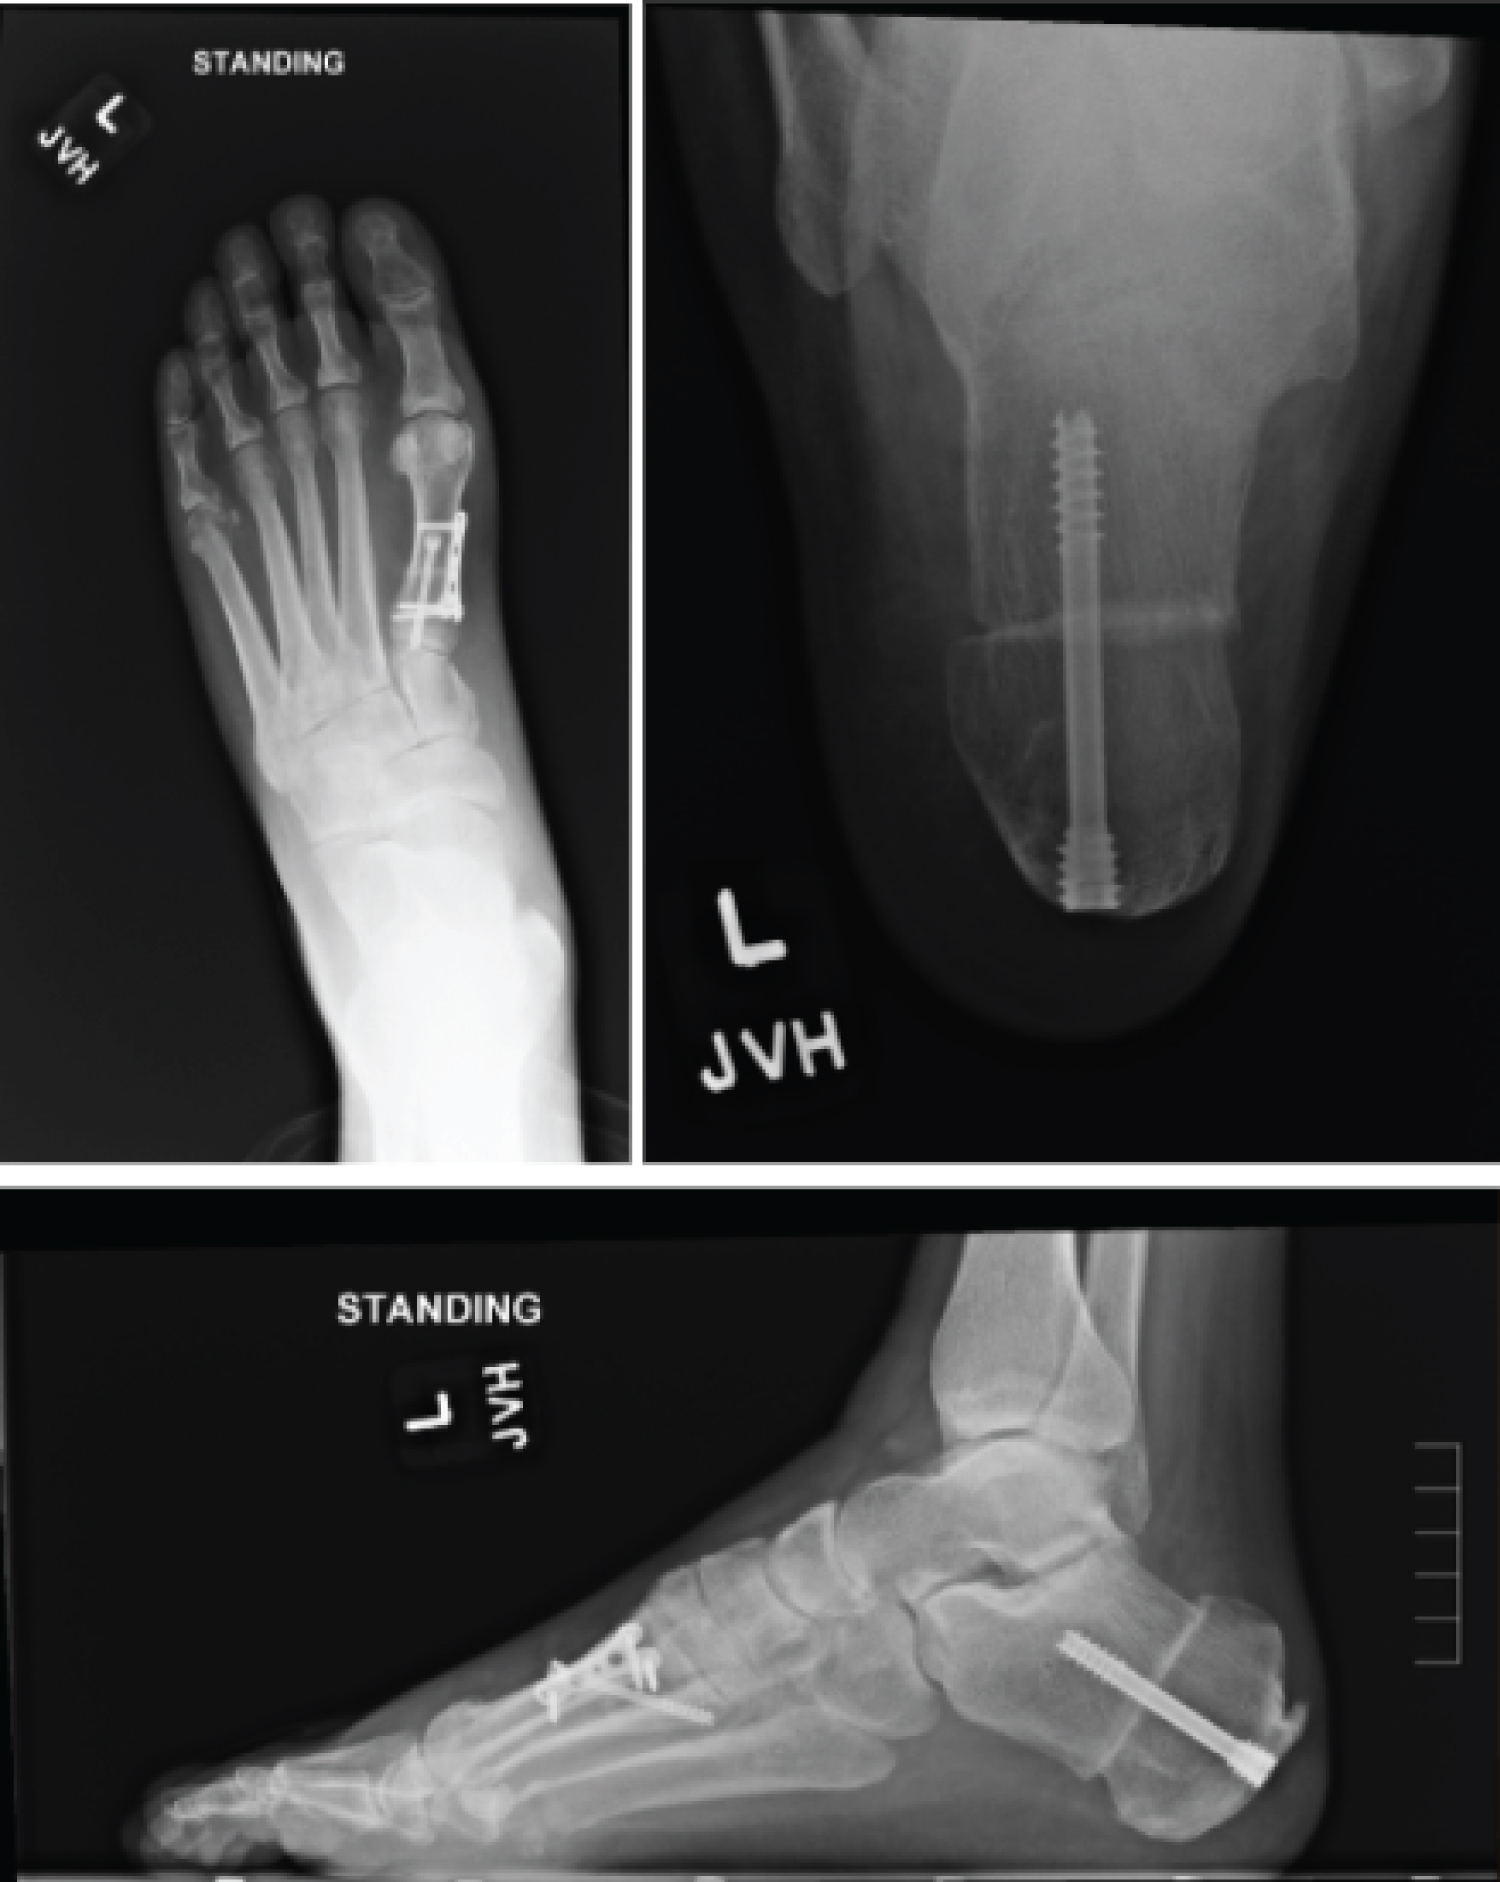

After medical optimization, the patient's left foot was surgically corrected with the following procedures, respectively: Steindler stripping, Dwyer, posterior tibial tendon transfer to lateral cuneiform, and dorsiflexory wedge osteotomy of the 1st metatarsal. The patient was placed into a posterior splint and was made non-weight bearing. The patient was transitioned to a CAM boot at the first postoperative visit, however remained non-weight bearing for a duration of 6 weeks. After postoperative week 6, radiographs of the foot were taken and demonstrated union of osteotomy sites (Figure 6). The patient was then started with gradual weight bearing, transition out of the CAM boot, and formal physical therapy.

Figure 6: Postoperative radiographs of a patient with CMT who underwent reconstructive surgery. View Figure 6

Now at two year follow up, the patient is doing well with no pedal complaints or functional limitations on the operative side and wishes to have the contralateral side surgically corrected (Figure 7).